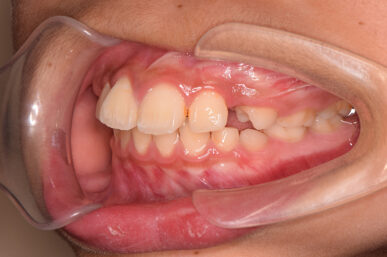

• Before

治療開始が遅くてこのままでは犬歯の生えるスペースが不足していて八重歯になるところでしたが、アライナー矯正で素早く歯を動かして犬歯が生えてくるスペースを作ることで八重歯にならずに済みました。

八重歯のケースは永久歯の抜歯が必要になることもありますが、避けることができました。